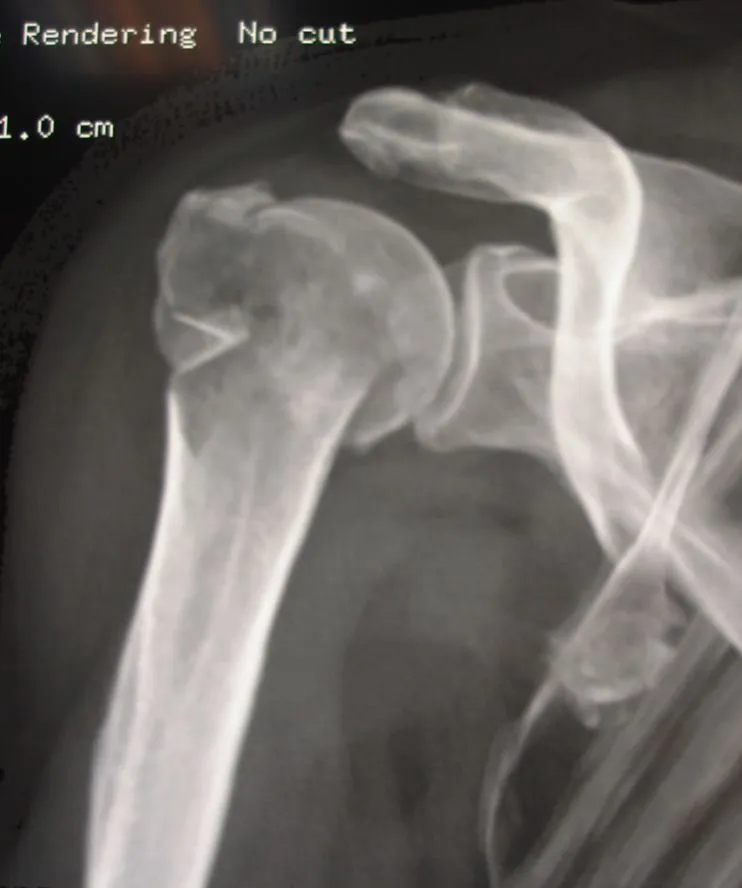

fracture luxation de l'épaule

prothèse inversée pour fracture de l'épaule